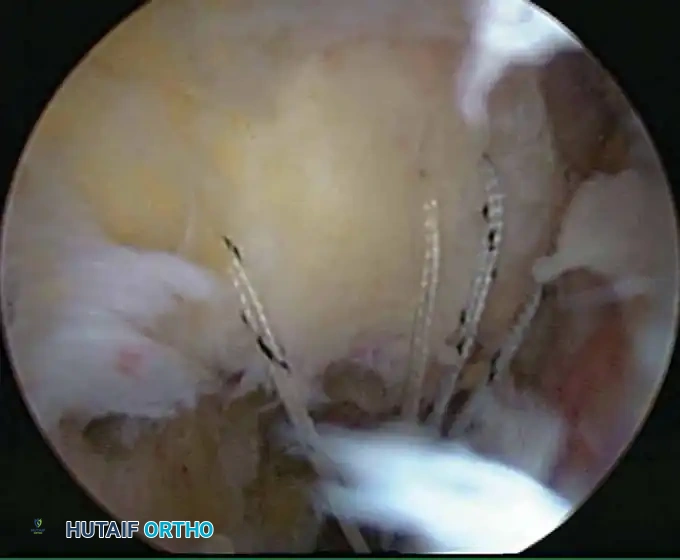

Once diagnostic evaluation is complete and hemostasis is secured, the therapeutic phase commences. Whether performing a SLAP repair, a Bankart stabilization, or a rotator cuff repair, the principles of tissue mobilization, anatomical footprint restoration, and secure biomechanical fixation remain paramount.

Modern arthroscopy relies heavily on suture anchors (biocomposite or all-suture constructs) and advanced arthroscopic knot-tying or knotless techniques. The ability to pass sutures through retracted, fibrotic tissue and secure them under appropriate tension without strangulating the microvascular supply is the hallmark of a master arthroscopist.